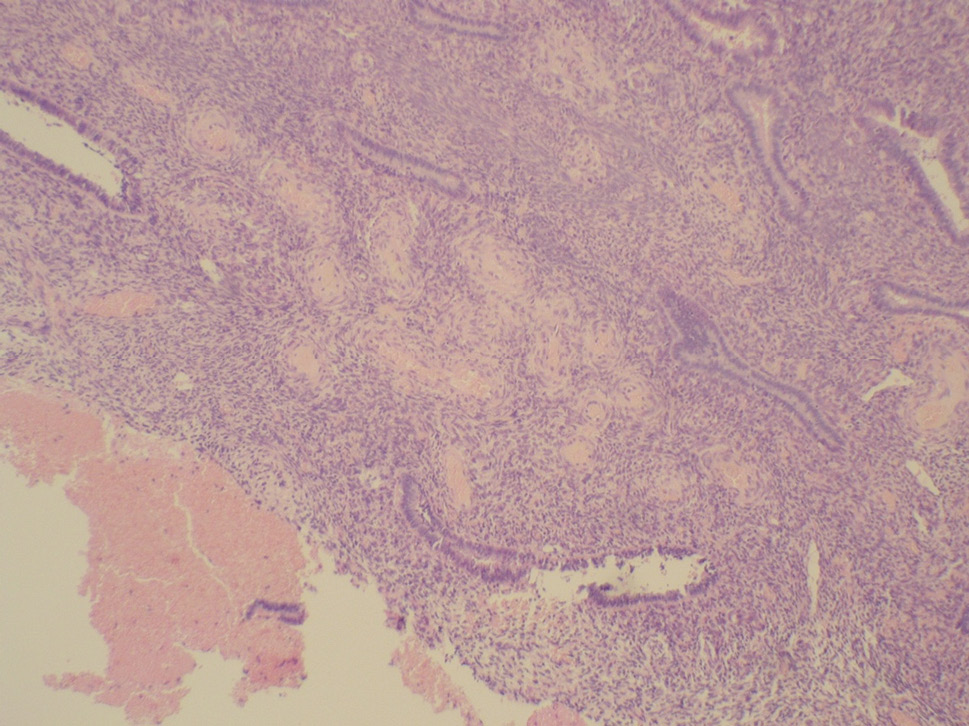

In the reproductive period, polyps were mainly small and medium in size and represented by the functional layer of the endometrium. A morphological study revealed glandular (81.8%) and glandular-fibrous (18.2%) polyps (Fig. 2).

Fig. 2. “Vascular pedicle” of the glandular-fibrous endometrial polyp in a woman of reproductive age (hematoxylin and eosin staining at ×100 magnification)

Рис. 2. «Сосудистая ножка» железисто-фиброзного полипа эндометрия у женщины репродуктивного возраста (окраска гематоксилином и эозином, увеличение ×100)